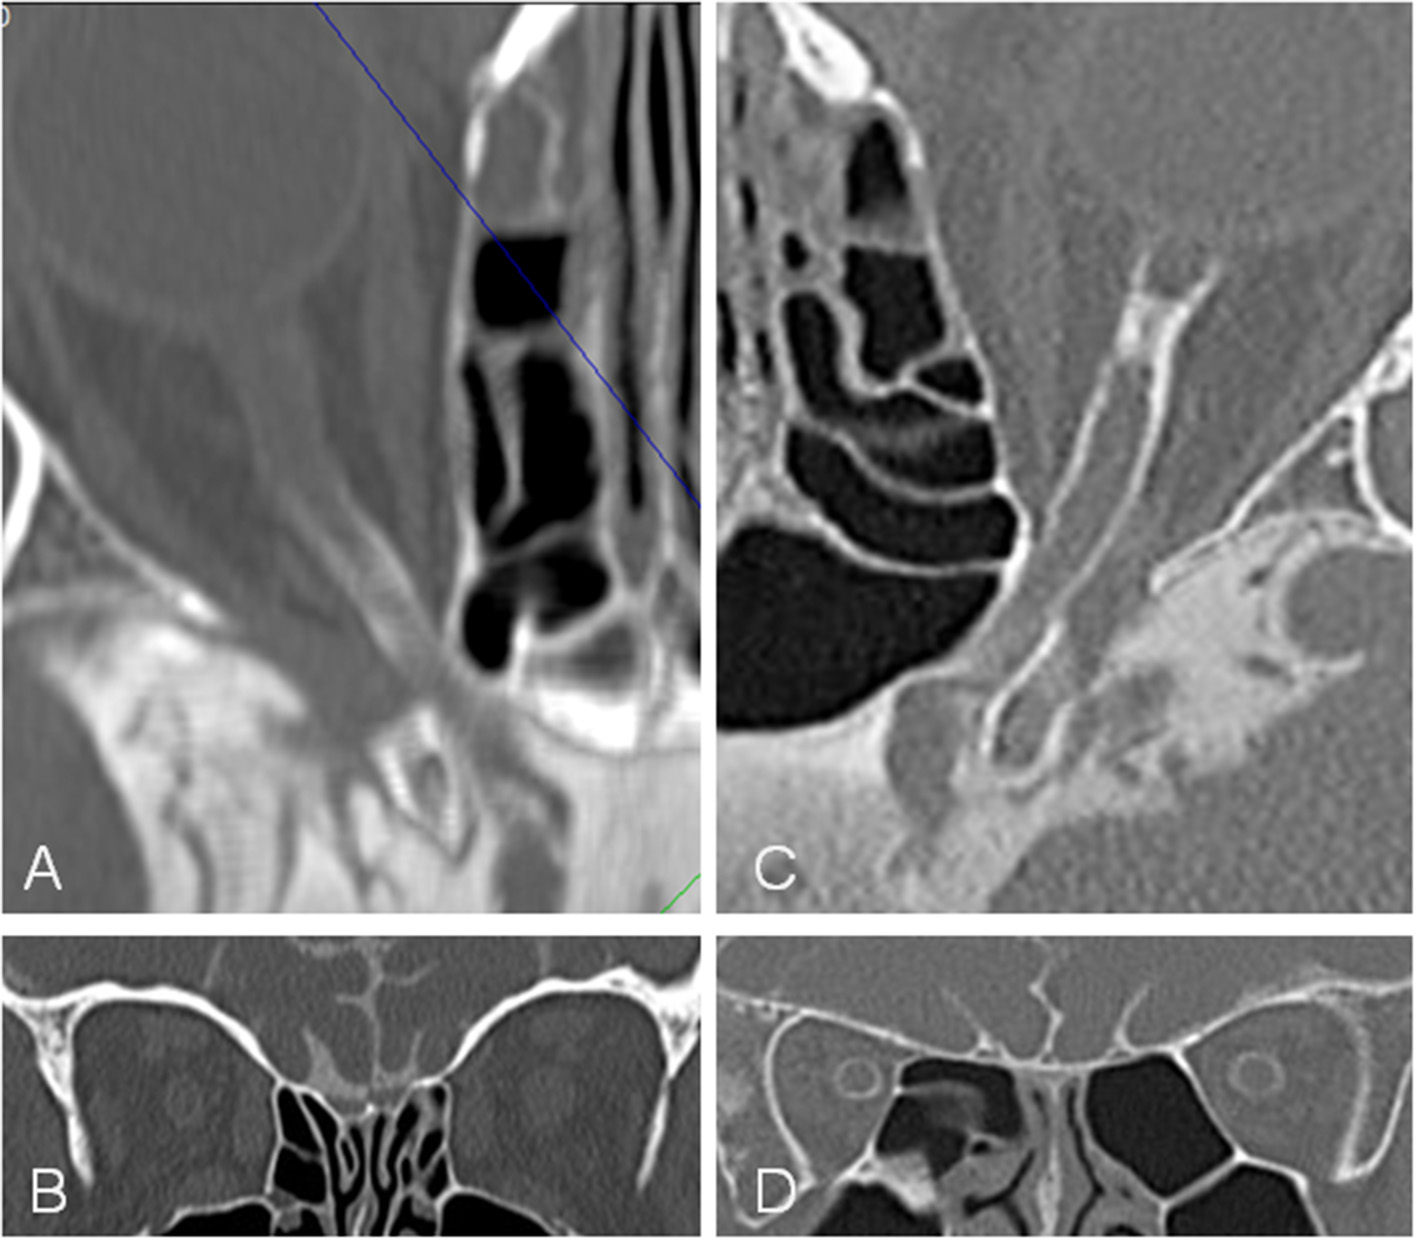

Figure 5

Computed tomographic (CT) cisternography in a patient with idiopathic intracranial hypertension (IIH) and papilledema and a control subject. In the patient with IIH (A,B) contrast loaded cerebrospinal fluid (CLCSF) inflow stops behind the optic canal while in the control subject (C,D) contrast loaded cerebrospinal fluid (CLCSF) flows into the orbital segment to the globe.